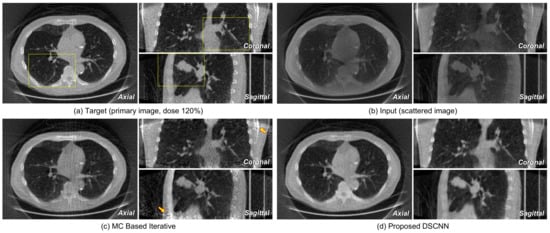

Figure 11 shows the axial images taken from reconstructed volumes with specific profile data. The superiority of the proposed DSCNN against MC-based method is evident from both the sliced image and the profile. Figure 12a,b represents the axial, coronal, and sagittal images of a target and its corresponding input scattered image, respectively. Figure 12c shows that no additional artifact is generated from the proposed DSCNN, as opposed to the MC-based iteration method in Figure 12d. However, additional artifacts are seen in the coronal and sagittal images at the arrow-indicted parts of the images from the MC-based iteration method. The regions enclosed by the yellow rectangles in Figure 12 are magnified in Figure 13. The proposed DSCNN enhances the bone boundary in the axial image (arrow), recovers the morphological information in the coronal image (circle), and well reveals the shading in soft structure in the sagittal image (arrow). The MC-based iterative method produces additional noise in the soft structure.